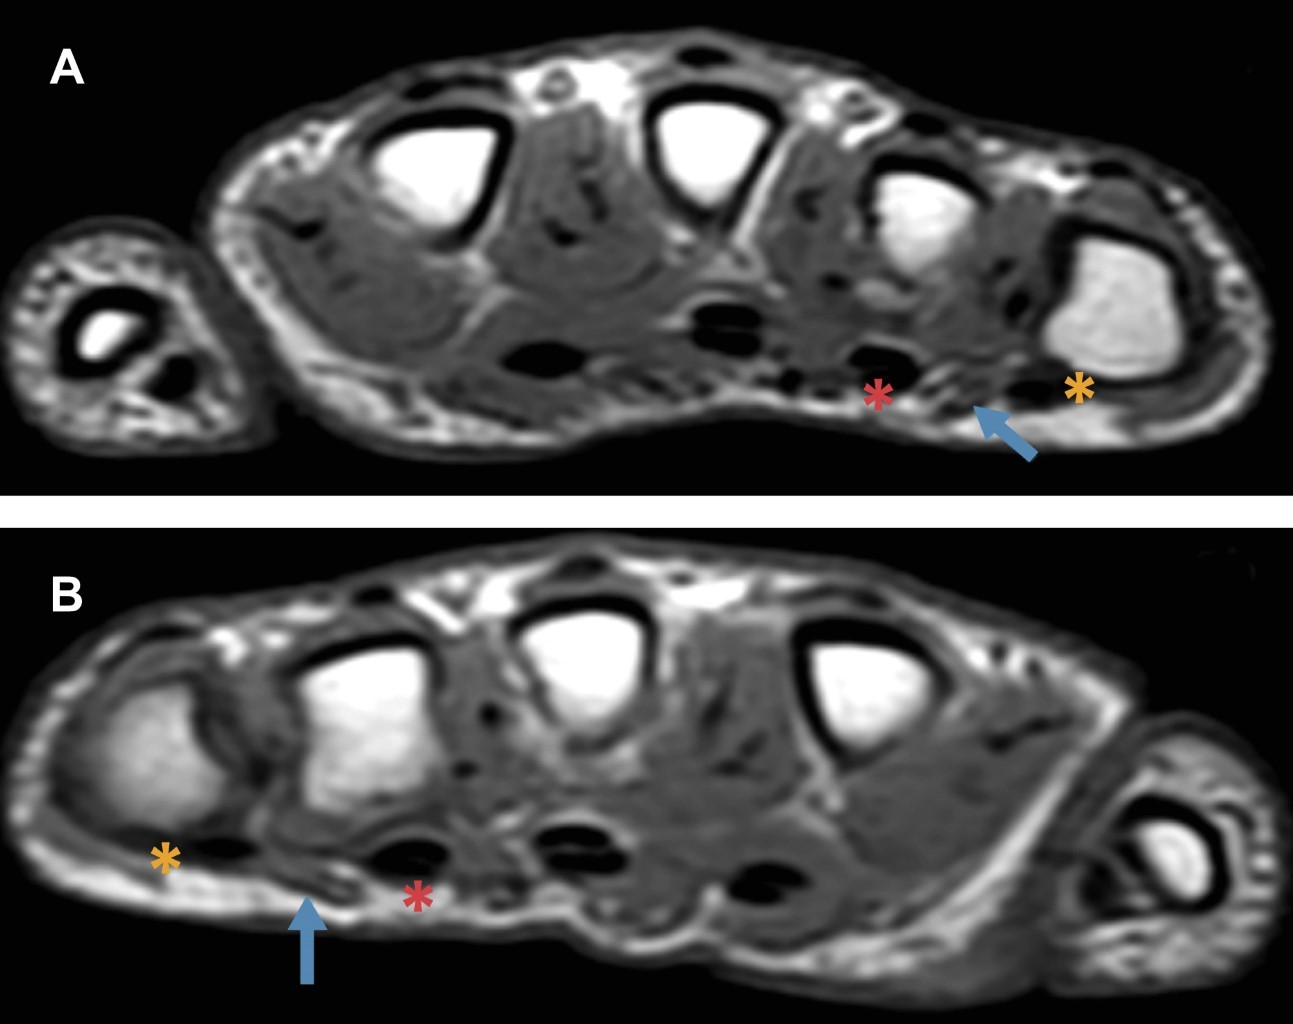

Masculino de 15 años de edad, que presenta deformidad del dedo meñique de ambas manos. No tiene antecedentes de traumatismos, patologías o síndromes congénitos. Nadie más en su familia presentaba dicha morfología en los dedos. En el estudio de resonancia magnética (RM) se observó deformidad del quinto dedo por hiperflexión de la articulación interfalángica proximal en forma bilateral (Figura 2). El vientre muscular del cuarto lumbrical presenta un curso superficial en relación a los tendones flexores superficial y profundo, secundario a una inserción anómala, con disminución en su diámetro en el plano axial (Figura 3). Todos los hallazgos son más evidentes en el dedo meñique de la mano derecha. Las articulaciones interfalángicas distales y metacarpofalángicas presentan hiperextensión compensatoria.

Favril y colaboradores publicaron una serie de tres casos con imágenes de RM y ultrasonido, donde identificaron que los músculos lumbricales son la principal estructura afectada. Estos músculos pueden tener una inserción aberrante hacia el tendón flexor superficial, un curso aberrante o una disminución en su grosor o longitud.1

Actualmente la RM es de gran utilidad, no sólo en la valoración de las alteraciones de los músculos lumbricales, sino también en otras estructuras relacionadas con la deformidad como los tendones flexores superficiales y profundos, la placa volar, los ligamentos colaterales y tejidos blandos superficiales.